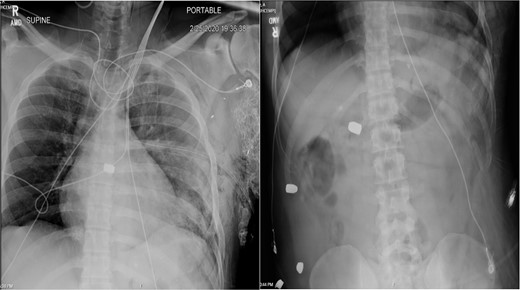

In the OR, exploratory laparotomy, right nephrectomy, liver packing, and pericardial window were performed. The pericardial window was negative for blood. With no suspected cardiac injury, intraoperative fluoroscopy (Fig. 1) and transesophageal echocardiogram (TEE) (Fig. 2) were used to locate the bullet. It was suspected to be intravascular secondary to venous embolism from the retro-hepatic inferior vena cava (IVC). Cardiothoracic surgery was consulted for removal of the bullet. With abdominal hemorrhage controlled, the surgeons agreed the patient was an acceptable risk for anticoagulation and cardiopulmonary bypass. Sternotomy was performed, the patient was placed on cardiopulmonary bypass, and the bullet was removed through a right atriotomy.

Intraoperative TEE demonstrating the intravascular bullet in the IVC.

Case 1 involved a stable patient with a single GSW to the left back and a retained bullet over the right ventricle. The trauma team identified the bullet overlying the cardiac silhouette and performed a CT scan to determine its trajectory. The scatter artifact complicated localization, but a pericardial window excluded cardiac injury. Intraoperative imaging (fluoroscopy and TEE) revealed a venous bullet embolism from the retro-hepatic IVC to the right ventricle. The bullet was mobile on fluoroscopy, and TEE provided the best imaging. The trauma and cardiothoracic surgeons discussed bullet removal timing, considering the patient’s stability and heparinization needs. They opted for immediate removal due to the potential lethality of pulmonary artery embolism. The operation was successful, requiring only one surgery for definitive management. This case highlights the success of immediate bullet removal in hemodynamically stable, asymptomatic patients with venous embolism.